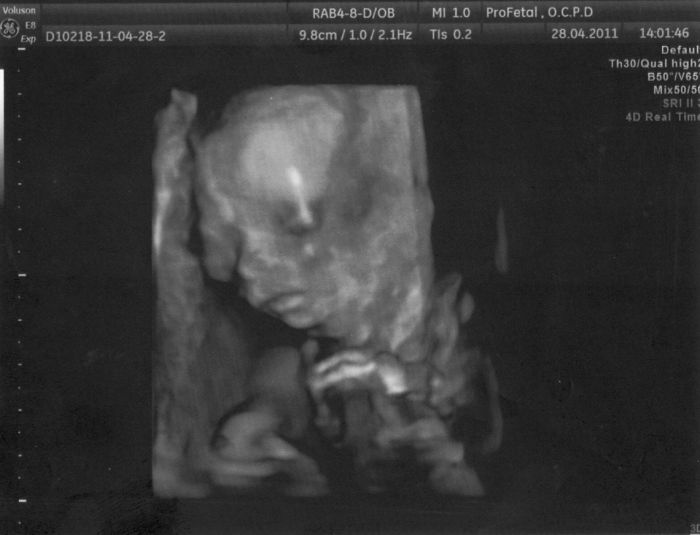

Ahoj holky, ráda bych se k vám přidala. Čekám své první vytoužené mimčo. Termín porodu mám 20. září. Už mám potvrzeno, že to bude holčička.